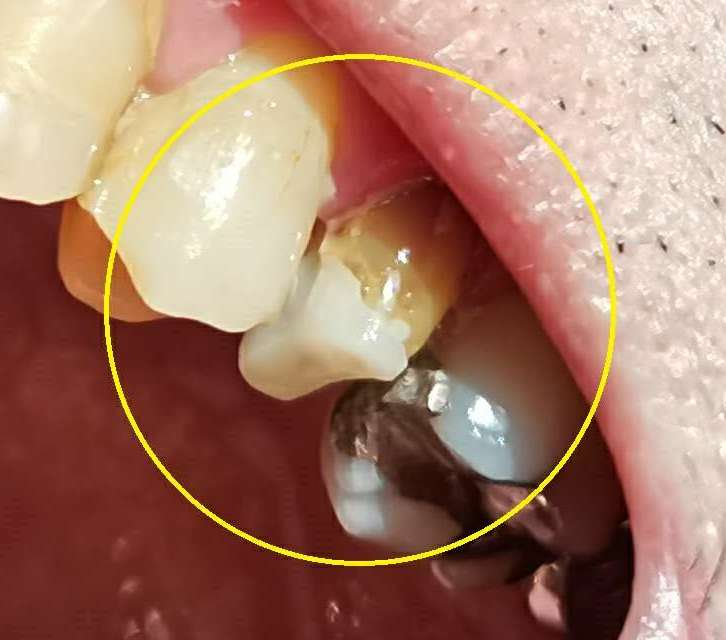

左上5番に土台をはめた。

(次回、型取り)

今日は土台をはめただけ。

次回は時間が掛かる、